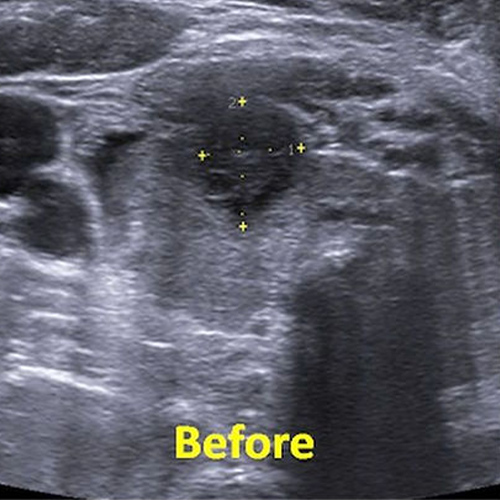

A 34 year old female with a 67mm solid thyroid nodule underwent radiofrequency ablation.

The max diameter of the nodule was 43mm at 3 months. Affer additional alcohol ablation, the nodule was reduced to 20mm in size corresponding to more than 90% volume reduction.

The patient became symptom-free and the appearance of the neck returned to normal.